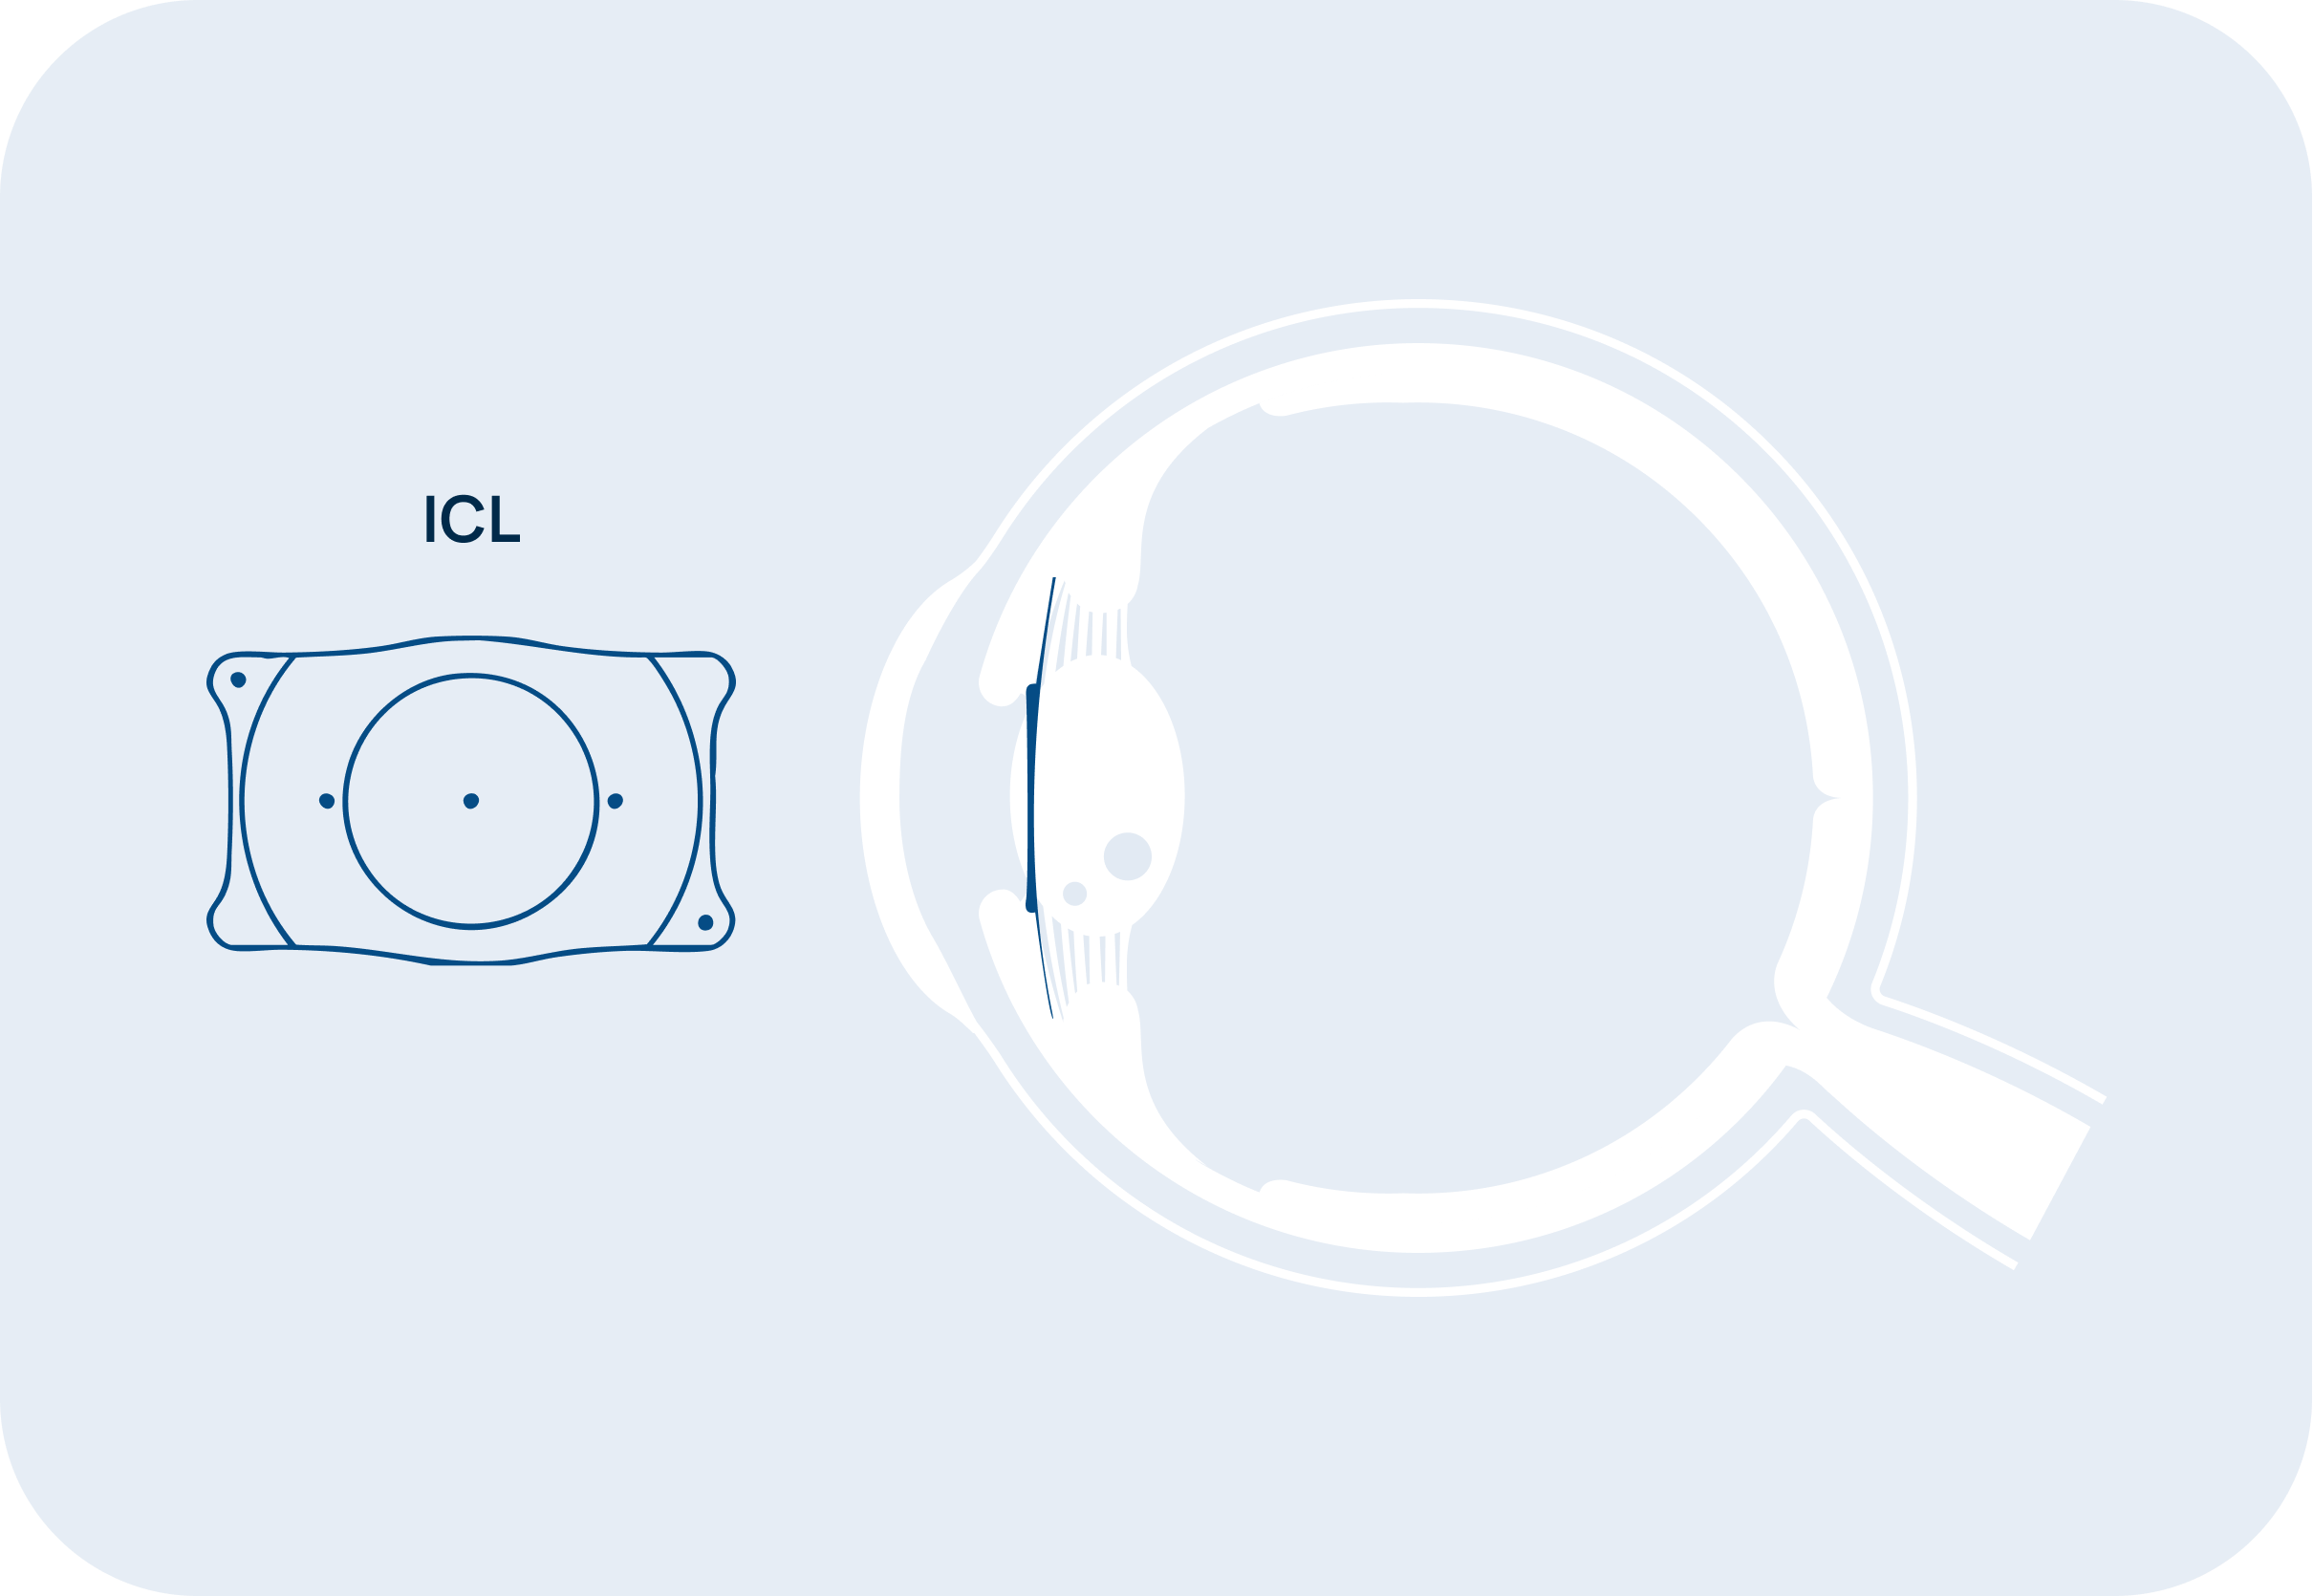

L’impianto di lenti intraoculari ICL (Implantable Collamer Lens) è un trattamento chirurgico avanzato per correggere difetti visivi come la miopia, l’ipermetropia e l’astigmatismo elevati, offrendo una soluzione alternativa alla chirurgia laser refrattiva.

Questa tecnica prevede l’inserimento di una lente speciale, personalizzata sulle esigenze del paziente, tra il cristallino e l’iride, senza rimuovere o danneggiare alcuna parte dell’occhio.

È definita ‘lente fachica’, perché la lente non sostituisce il cristallino, a differenza delle lenti utilizzate nella chirurgia della cataratta, ma si colloca a pochi micron da esso senza danneggiarlo.

L’impianto di lenti ICL (Implantable Collamer Lenses) è una procedura chirurgica che impianta una lente all’interno dell’occhio per correggere difetti visivi come miopia, ipermetropia e astigmatismo elevati. A differenza della chirurgia laser, le ICL non richiedono la rimozione di tessuti oculari, ma vengono inserite tra l’iride e il cristallino, migliorando la vista senza alterare permanentemente l’occhio.